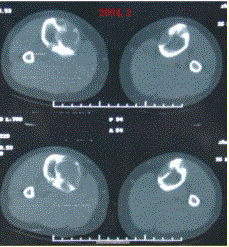

问题 患者女,20岁,右小腿疼痛1周。行双小腿正侧位CR,并行双小腿CT及MR扫描,见下图。 关于病变发生部位,叙述正确的是

选项 A.双侧胫骨干骺端 B.双侧胫骨骨干髓质部 C.双侧胫骨骨干皮质部 D.双侧胫骨骨骺 E.双侧胫骨周围软组织

答案 B